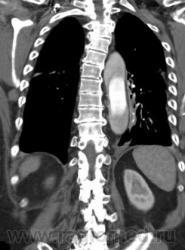

Рассоение аорты тип "A". Восходящий, нисходящий отдел, дуга, переход на брахиоцефалы...

Согласна. Только насчет брахиоцефала возражаю. Его не видно. То, что на 2 срезе, может оказаться верхней точкой дуги аорты. Нужны еще реконструкции, фронтальные например или весь объем.

Ага, я видно поторопилась. Когда я писала, были только аксиалы и то не все. Теперь, когда появились фронтальные реконструкции вижу переход на устье плечеголовного ствола. Есть признаки разрыва: жидкость в плевральной полости и немного в легком.

Ну, в данном случае понятно, что просвет который законтрастирован слабее - является ложным. Но в некоторых случаях, довольно сложно определить истинный и ложный просвет. В этом могут помочь: 1. Истинный просвет обычно меньше на аксиалах 2. СимПтом 'клюва' или 'beak sign" - наиболее характерный признак для ложного прросвета ( четко представлен в данном случае)то есть есть клювообразные выпячивания по периферии ложного просета в сторону истинного. 3. Cobweb sign - тоже характерен для ложного просвета ( мелкие 'ниточки' от отслоенной интимы в сторону ложного просвета. Другие признаки менее специфичны Доольно сложно иногда бывает отличить где исинный а где ложный просвет прихронических аневризмах.